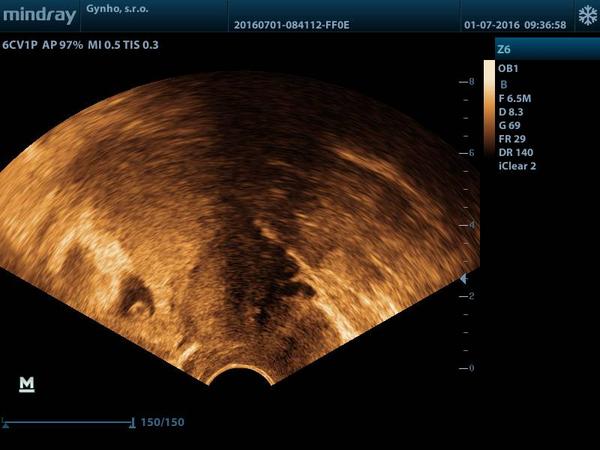

holky sem po ivf kde mi texl zavedl 2 embria dnes sem 9 tt foto je v 4 tt myslíte ze tam sou dve nebo jedno muj gyndar rikal ze vidi jen jedno ale ze je to velice brzo dekuji za radu

@barisej netroufnu si to posoudit. Dutinku vidim jednu, ale jestli je to uzv z 4tt je opravdu brzo. Ted jsi v 9tt to so tatim neměla delany uzv na průkaz srdeční akce?

@barisej Ve 4. týdnu z UTZ určitě jedno nebo dvě nezjistí, ale teď už musíš mít 100% srdeční akci a ta je buď jedna nebo dvě.